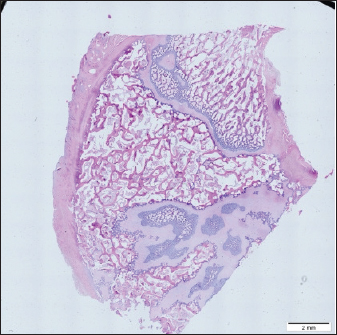

To get a comprehensive histological image of the sample, we had to merge all views into a single image using the Olympus Cell-Sens Dimension software (Fig. 2).

Fig. 2. Merged histopathology sample.

Histomorphometry

Different L1 and L2 vertebral parameters were investigated (Fig. 4). The lowest BV/TV ratio of a L1 vertebra was 7.88% and the highest was 23.08%. In the study of L2 vertebrae, the lowest BV/TV was 11.58% and the highest was 23.7%.

The thickness of the trabeculae in the L1 and L2 lumbar vertebrae was also assessed independently. The smallest trabecula in L1 measured 17.34 microns and the biggest measured 31.88 microns. The L2 vertebrae had a minimum trabecula thickness of 18.76 microns and a maximum of 30.75 microns (Fig. 5). If trabeculae are damaged or crushed in, they will be able to withstand a much smaller load and so have a greater likelihood of breaking.